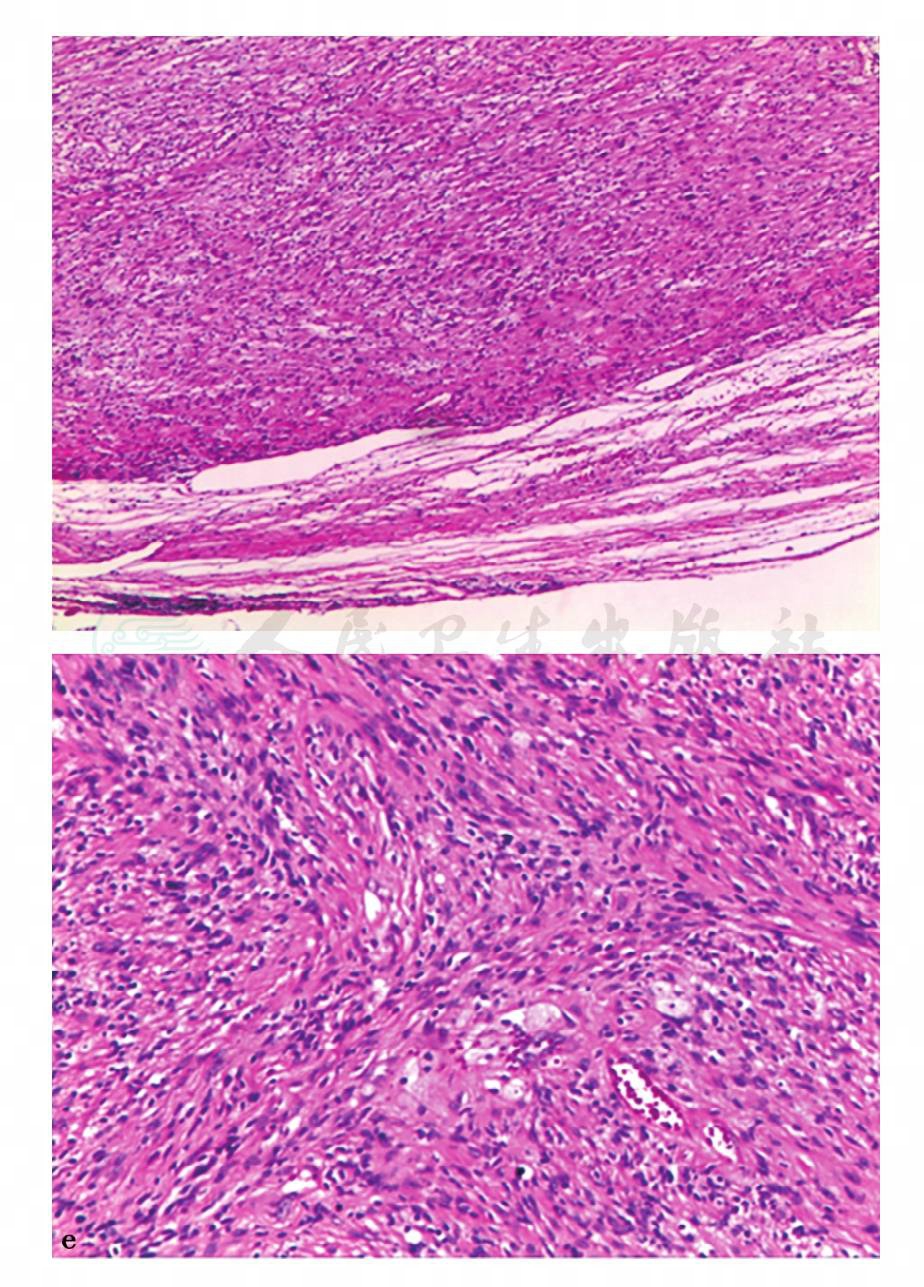

图17 e,病理诊断:(胰头部腹膜后)神经鞘瘤